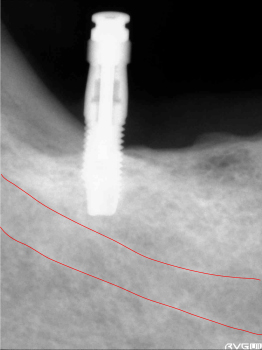

エミネオの本体を挿入します。下歯槽管までの安全性を確認します。まだ余裕があるいのが確認出来ます。 | ||

骨の深さが9mm程度だったので、ちょうど下歯槽管の真上ぐらいで止めます。 1本目終了。 |